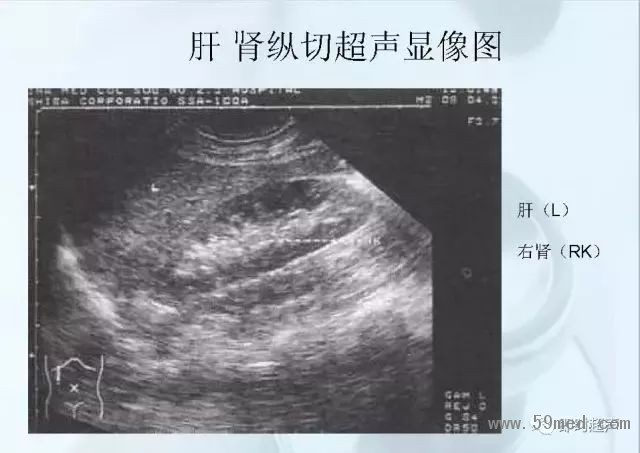

新聞中心 收藏!正常B超解剖圖譜,超實用!